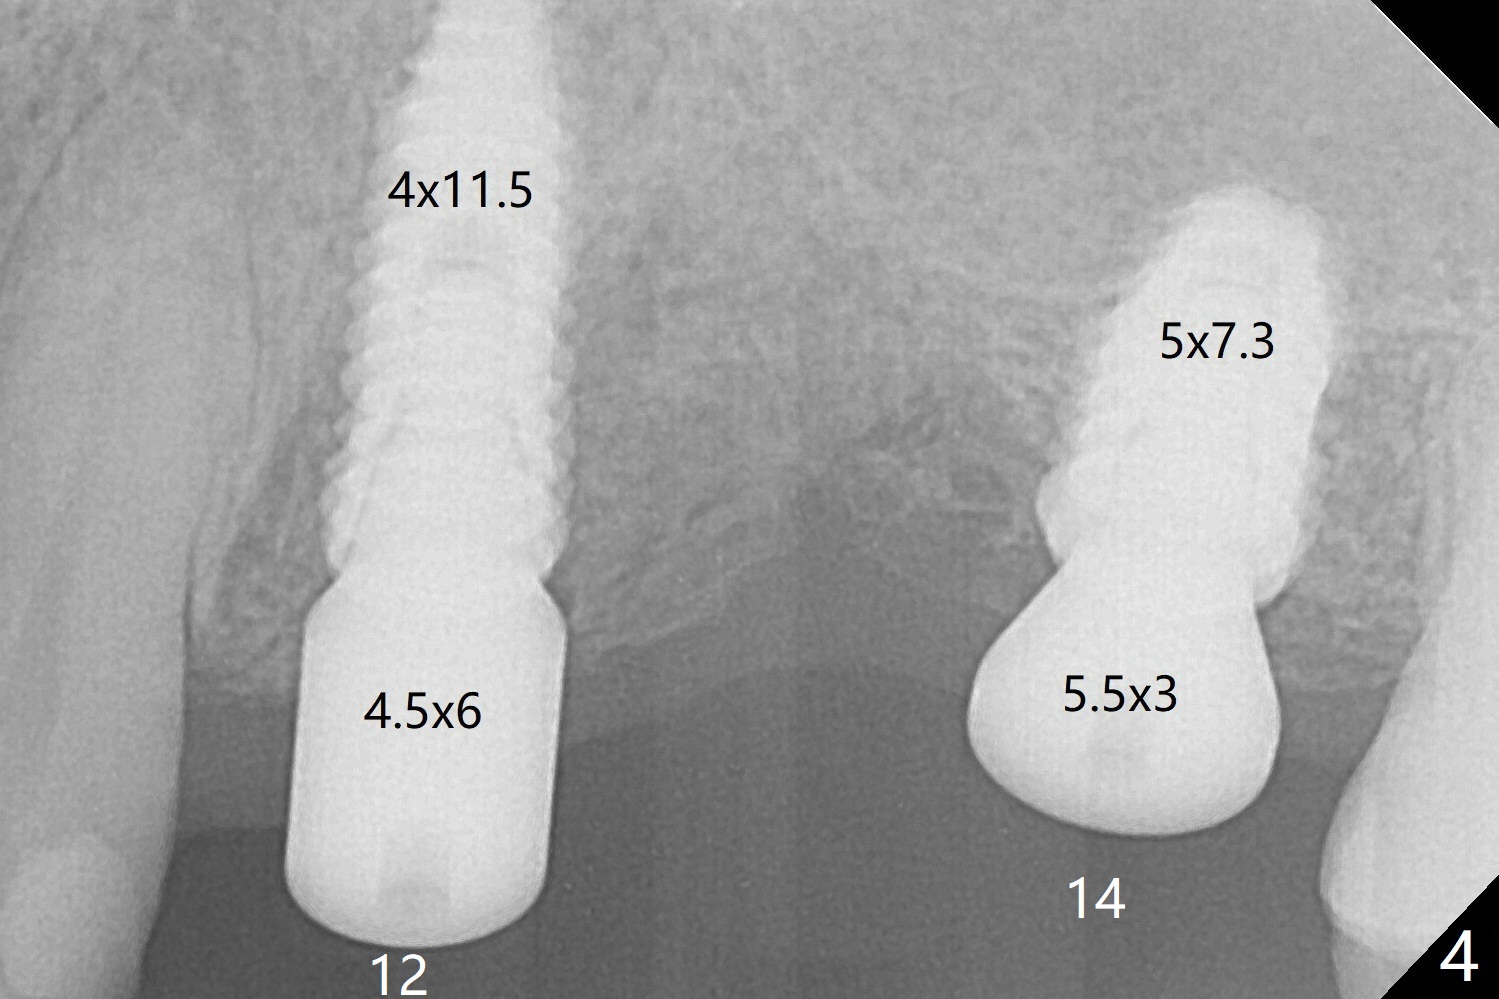

The implants at #12 and 14 are placed 1 month later (Fig.4). The 4 implants have impression (Fig.5,6) and cementation (Fig.7-9) at the same time. Although the upper FPD is able to be removed after cementation in the mouth (Fig.7), the abutment screw cannot be tightened >20 Ncm (Fig.8). The tooth #15 is tender early after crown/FPD cementation and needs occlusal adjustment twice. The crown of #18 dislodges eight months post cementation (Fig.11 taken after recementation). There is no bone loss at #13 and 15 (Fig.10), while the bone density increases around the implants at #18 and 19 eight months post cementation (Fig.11). The abutment screw at #18 become loose 1.5 years post cementation; after proximal surface trimming twice (<), the abutment remains incompletely seated (Fig.12,13). With suspicion of soft tissue block (Fig.13 *), a small abutment with longer cuff is completely seated (Fig.14).